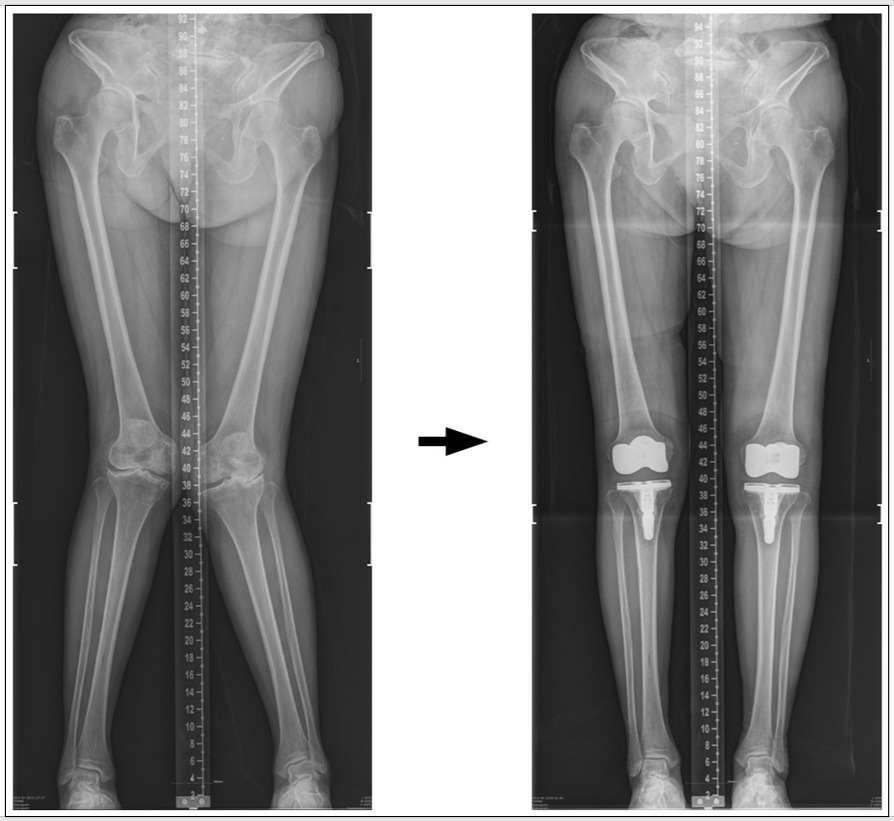

연골이 다 닳아 뼈와 뼈가 부딪치는 말기 관절염의 가장 확실한 치료법은 인공관절 수술입니다. 우리나라에서 한해 약 10만 건의 수술이 시행되고 있으며, 이 수치는 해마다 증가되고 있습니다 [28]. 최후의 방법인 인공 관절에도 몇 가지 종류가 있습니다. 인공 관절 ‘전치환술’은 무릎 연골의 손상된 부위 크기와 상관없이 무릎 관절 전체를 완전히 바꾸는 광범위한 수술이라 술 전 심한 통증을 잡는 데는 탁월한 효과가 있습니다. 하지만 술 후 재활치료 과정이 쉽지 않으며, 어느 정도 시일이 경과한 후에도 무릎의 구부리는 각도가 수술 전보다 못하거나 쪼그려 앉을 수 없어 불만스러워하는 환자들이 드물지 않게 있습니다. '전치환술' 수술받은 환자의 약 20%는 술 후에도 통증 및 기능 장애가 남아 수술 결과에 만족 못한다는 보고도 있습니다 [29].

'전치환술' 술 중 사진 & 술 후 X-ray

* 아래 사진 -> 심한 '오'자형 다리의 73세 여성 수술 전 후 사진.

심한varus 정정순 술전(595471). (1)....jpg

* 아래 사진 -> 심한 '엑스'자형 다리의 65세 여성 수술 전 후 사진.

심한 valgus 김영숙 술후.......jpg